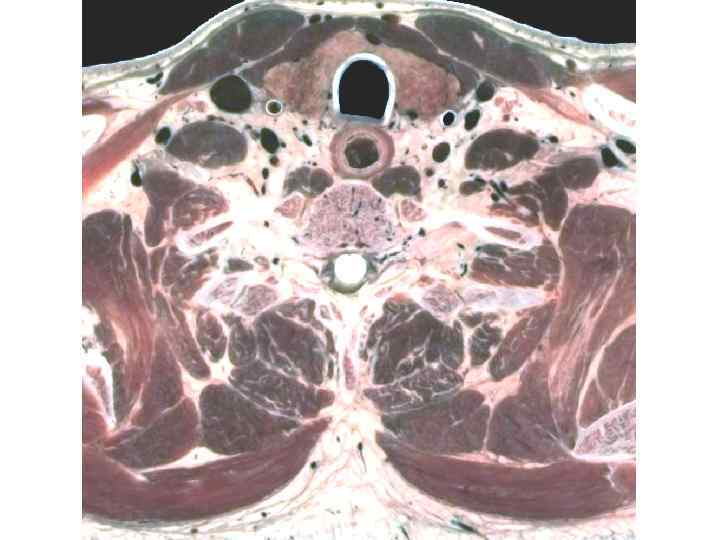

1 - кожа; 2 - подкожная клетчатка, 3 - апоневроз надчерепной мышцы, 4 - подапоневротическая клетчатка, 5 - надкостница, 6 - поднадкостничная клетчатка, 7 - наружная пластинка костей свода черепа, 8 - губчатое вещество, 9 - внутренняя пластинка, 10 - эпидуральное пространство; 11 - твердая мозговая оболочка головного мозга; 12 - субдуральное пространство; 13 - паутинная оболочка головного мозга; 14 - подпаутинное пространство, заполненное цереброспинальной жидкостью; 15 - мягкая мозговая оболочка. Послойное строение свода черепа